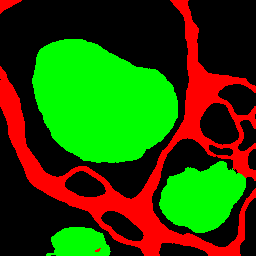

Figure 6: Segmentation results on Drosophila dataset

4.3.2 Results on Drosophila Cell Images

As shown in Table 3, the proposed method improved the accuracy compared to the conventional methods in many classes. In particular, our proposed AML-Net and Top-Down PDA-Module improved the accuracy of synapses, which is the most difficult class. Top-Down PDA-Module is a top-down attention mechanism using ground-truth, and it is considered that the accuracy is improved due to its ability to create attention maps that explicitly strengthen particularly difficult synapses. In addition, the accuracy of ATA-Module was improved in many classes compared to conventional methods. From the feature maps obtained from the discriminator, it can be concluded that the ATA-Module contributes to the accuracy improvement because the similarity between pixels is appropriately enhanced by the ATA-Module. Therefore, AML-Net with the appropriate combination of Top-Down PDA-Module and ATA-Module can improve the accuracy of IoU for many classes. Deeplabv3+ with ResNet-50 as its backbone does not train well on Drosophila cell images, indicating that even successful models for scene segmentation are not effective for cell image segmentation. In addition, AML-Net has better IoU accuracy than FastFCN using ResNet-50.

The top image group in Figure 6 shows that Top-Down PDA-Module and AML-Net can accurately detect synapses that are easily over-detected by conventional methods. However, our method also caused excessive false positives for cell membrane and mitochondria on the right side. The false positives were probably caused by the fact that the input image shows something very similar to cell membrane and mitochondria. In the lower group of images, U-Net and Top-Down PDA-Module fail to detect mitochondria, and misidentify them as mitochondria in some cell membranes, while ATA-Module and AML-Net correctly identify mitochondria, reducing the number of undetected or false positives. Thus, we can see that AML-Net is able to recognize mitochondria by utilizing the advantages of both ATA-Module and Top-Down PDA-Module.